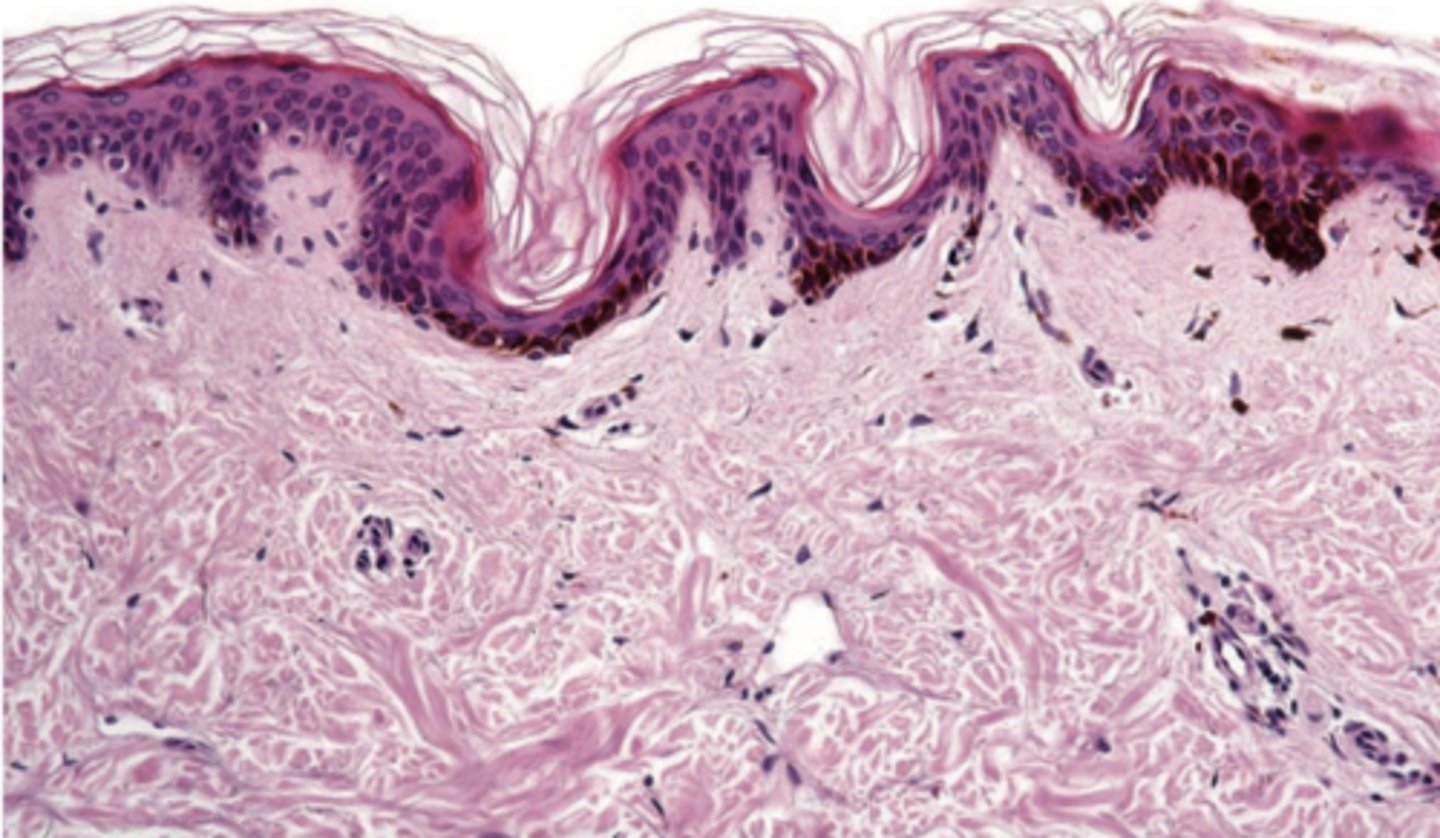

What pigmented lesion has these histopathologic features?

- Dendritic melanocytes throughout epithelium

- Thickened epithelium

- Increase in basal layer melanocytes

- Spongiosis and mild acanthosis

oral melanoacanthosis